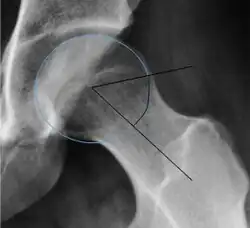

| Alpha angle | ![]() |

Degree of bulging of the femoral head-neck junction: In normal conditions there is a symmetric concave contour at the junction of the femoral head and neck. Loss of this concavity or bone bulging may lead to cam type impingement. The degree of this deformity can be measured by the alpha angle. Although it can be measured in the cross-lateral view, the 45° Dunn view is considered more sensitive and the frog leg view more specific in determining pathologic values. |

|